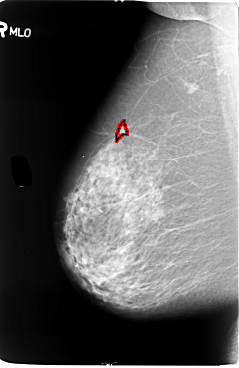

B_3057_1.RIGHT_MLO

FILE: B_3057_1.RIGHT_MLO.OVERLAY

TOTAL_ABNORMALITIES 1

ABNORMALITY 1

LESION_TYPE MASS SHAPE IRREGULAR MARGINS SPICULATED

ASSESSMENT 4

SUBTLETY 3

PATHOLOGY MALIGNANT

TOTAL_OUTLINES 1

BOUNDARY